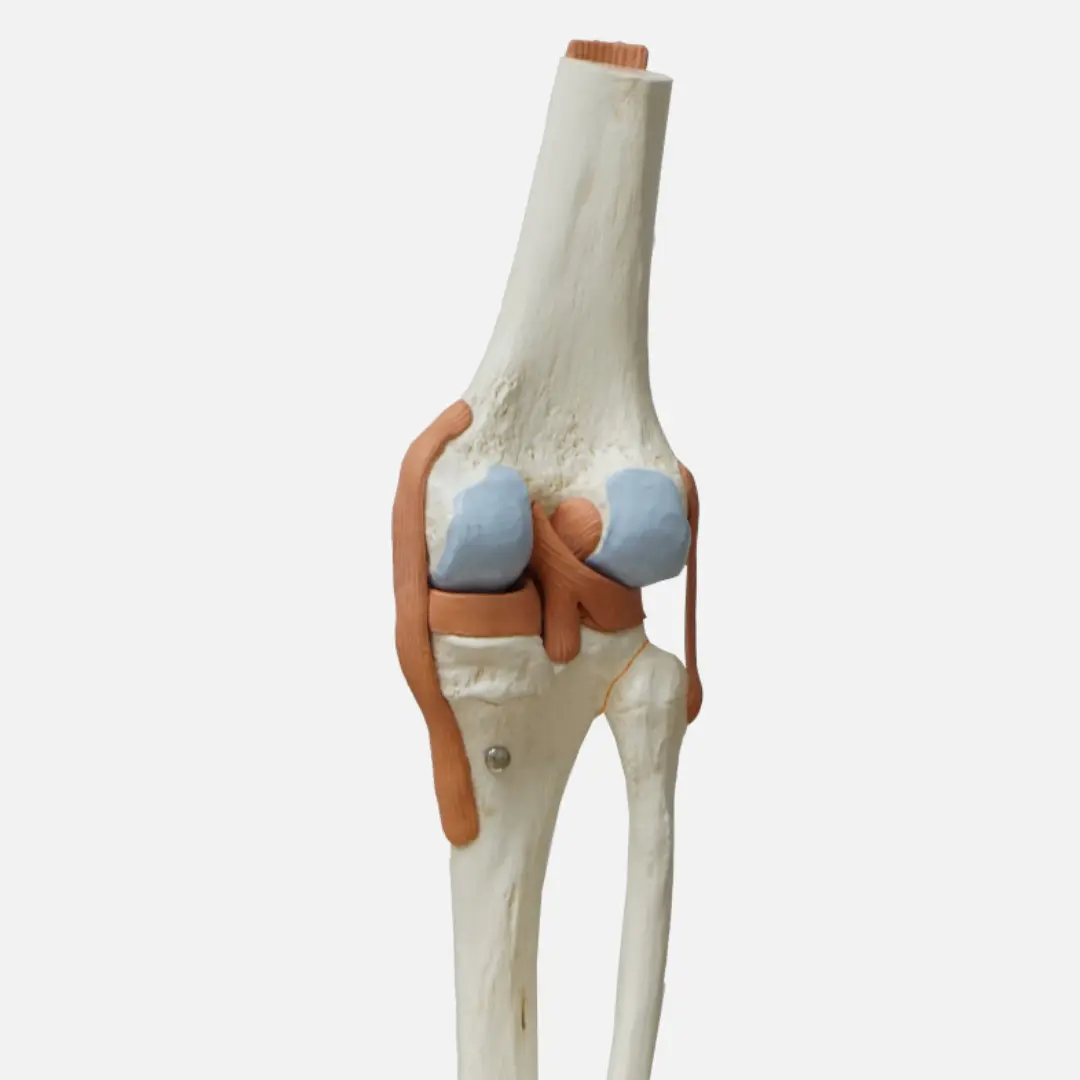

십자인대 파열은 무릎 관절 내에 위치한 중요한 인대인 전방 십자인대(ACL) 또는 후방 십자인대(PCL)가 손상되어 발생하는 부상이에요. 주로 스포츠 활동 중 갑작스러운 방향 전환, 급격한 감속, 무릎에 가해지는 직접적인 충격 등으로 인해 발생하며, 파열 정도에 따라 증상이 다르게 나타날 수 있어요.

전방 십자인대 파열 시에는 '뚝'하는 파열음과 함께 심한 통증이 즉시 발생하고, 무릎이 불안정하게 흔들리는 느낌을 받을 수 있어요. 부상 직후에는 무릎이 붓고 움직이기 어려워지며, 시간이 지나면서 통증은 감소하지만 무릎의 불안정감은 지속될 수 있어요.

후방 십자인대 파열은 전방 십자인대 파열보다 발생 빈도는 낮지만, 무릎 앞쪽으로의 직접적인 충격이나 과도한 꺾임 등으로 인해 발생할 수 있으며, 통증과 함께 무릎 뒤쪽의 뻐근함, 무릎을 굽히거나 계단을 내려갈 때 불편함이 나타날 수 있어요.